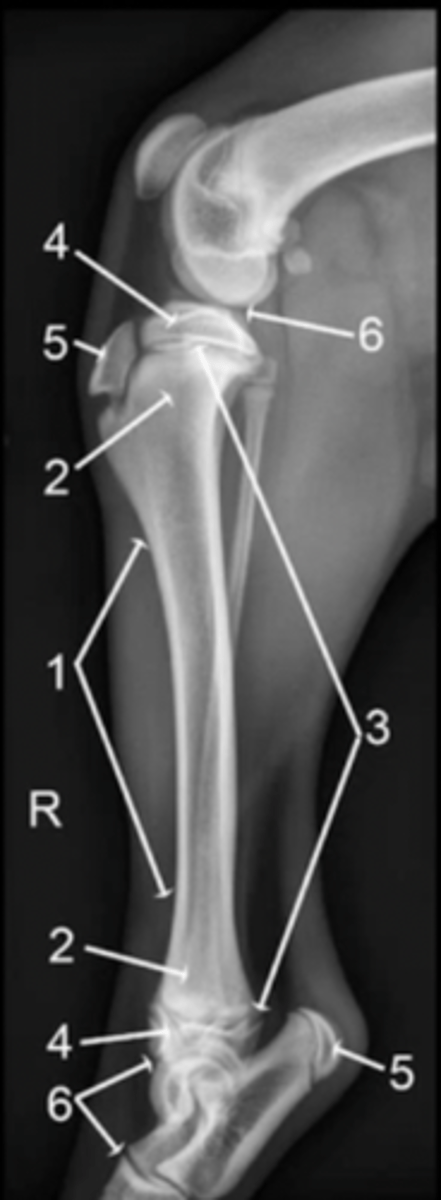

hind limb

What does the "H" label on this image indicate?

diaphysis

1

metaphysis

2

physis

3

epiphysis

4

apophysis

5

joint

6

epiphysis (or apophysis) from the metaphysis

The physis separates the ___________ from the __________

well-defined lucent line compared to surrounding bone

How will a physis appear radiologically?